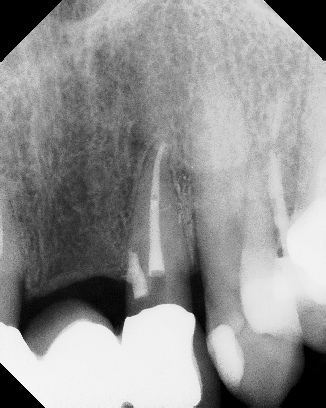

COMPLICATED ANATOMY LARGE LESIONS CALCIFIED CANALS PERFORATION / RESORPTION SEPARATED INSTRUMENTS SURGICAL CASES RETREATMENT / pOST REMOVAL OPEN APICES ACCESS THRU CROWNS Root Canal Case Portfolio